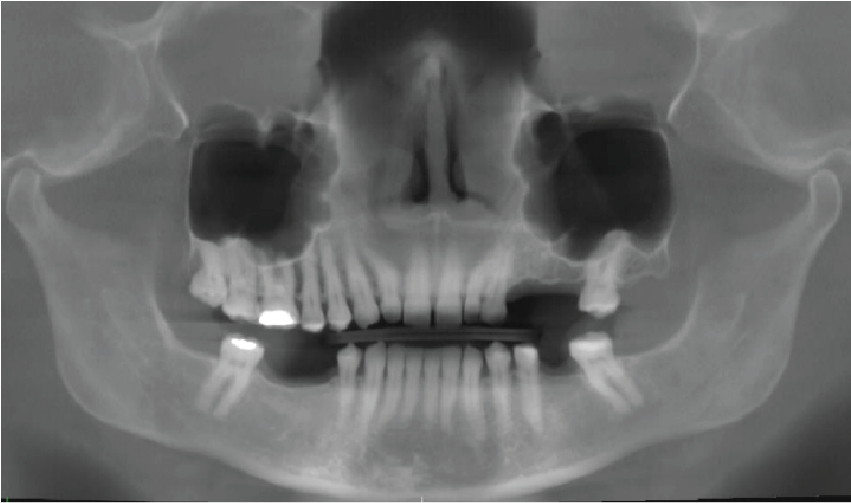

Periodontal bone levels are mainly normal or show mild bone loss, but there is greater bone loss associated with UR8 and UR7 and incidental finding of caries. UL4, UL5, UL6 sites have a mature alveolar ridge. No retained roots or bony pathosis. Selected images 3 are bucco-palatal cross-sections across the site. Bone height to the antral floor steadily falls moving distally across the site. There is a short transverse septum at the maxillary antral floor above the palatal side of UL5 site, which should not be relevant to any sinus lift procedure being planned. The alveolar bone quality appears satisfactory, with fairly dense trabeculation and well-defined cortices. The LL6 site has a mature alveolar ridge with no retained roots or bony pathothis. LL7 is mesially inclined, so that its crown overhangs the site. Selected images 4 are bucco-lingual cross-sections across the site. The alveolar ridge has a broad crest. There is a mild lingual undercut, with a lingual concavity present mesially in the site and in the premolar region. The lingual concavity of the submandibular fossa appears towards the distal end of the site. The ID canal is easily identified, lying quite low in the bone. The mental canal is in the plane of LL5. Bone quality is satisfactory, with well-defined thick cortices and fairly evenly trabeculated medullary bone.

Image 2

Panoramic reconstruction